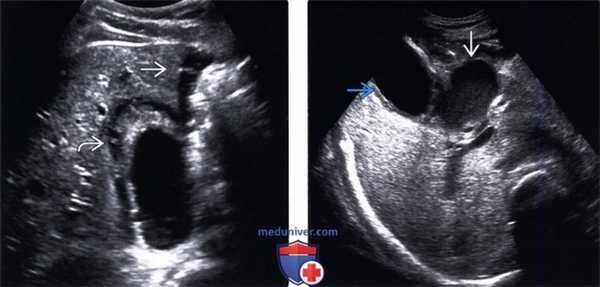

(Слева) На поперечной сонограмме определяется утолщение стенки желчного пузыря, в просвете которого находится крупный эхопенный конкремент с акустической тенью. Эти изменения, наряду с положительным сонографическим симптомом Мерфи, позволяют предположить острый холецистит (подтвердившийся во время операции).

(Левый) Положение пациента лежа на спине. На поперечном УЗ срезе визуализируются утолщенная отечная стенка желчного пузыря и смещающийся книзу под действием гравитации сладж (конкременты не видны). Обратите внимание на неоднородное скопление жидкости с медиальной стороны от печени.

(Правый) Случай перфоративного острого холецистита. Поперечный УЗ срез. С медиальной стороны от желчного пузыря с утолщенными стенками определяется скопление низкоэхогенных сигналов (абсцесс).